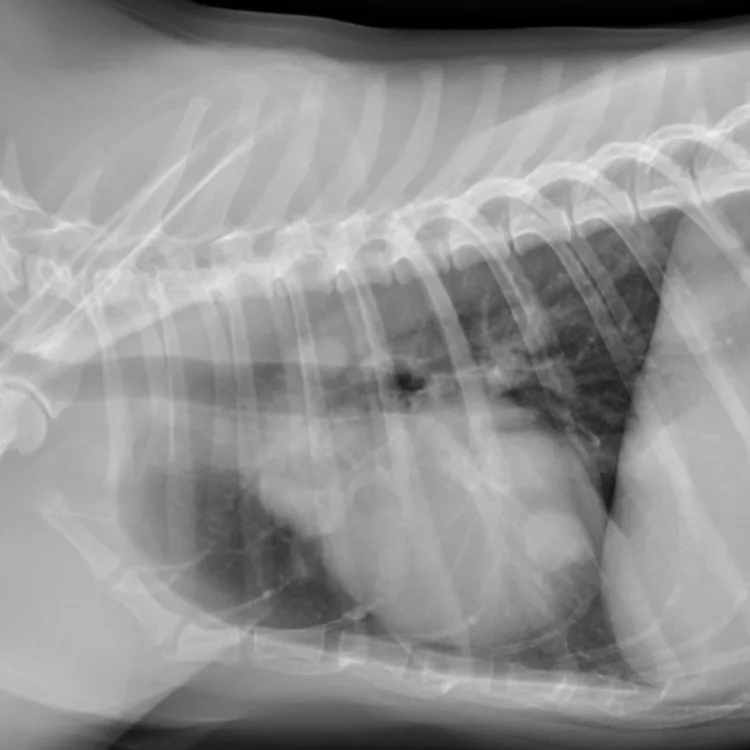

胸部レントゲン検査

肺転移の有無を評価します。